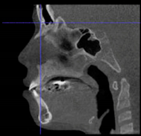

Three points determined the Acta plane: O, F right (FR), and F left (FL) (Table 2). Point O is the midpoint between the most craniodorsal point of the dorsum Sella and the most posterior dorsal point of the Basion in the midsagittal plane (Figure 1). Both points F are a result of the intersection between two lines: the line that connects the most inferior points of the lower orbital margins, right and left, and a line perpendicular to this line that runs through the most external points of the orbital margins, right and left (Figure 2). The new transverse reference plane, the Acta plane (Figure 2), is created by connecting the O-point (Figure 1) with FR and FL (Figure 2).

Figure 2.

(A) Construction of the F-points (right and left), frontal view. The F-points are originated from the intersection between the line connecting points A (the most inferior point of the lower orbit) and the perpendicular line to it that passes through points B (most external/lateral point of the Orbita). (B) Transverse view of the ACTA plane.

After determining the coordinates of the landmarks relevant to the Acta plane, the orientation of the skull with respect to the coordinate system of the DICOM could be determined. This orientation was defined by three angles: azimuth (the angle between the sagittal axis of the skull and the forward axis of the DICOM), elevation (the angle between the transversal axis of the skull and the mediolateral axis of the DICOM), and roll (the angle between the vertical axis of the skull and the vertical axis of the DICOM). These angles were transformed into a 4 × 4 rotation matrix [31], which served as an input for a custom-made computer script based upon algorithms provided by the Visualization Toolkit (VTK) (www.vtk.org) [32], accessed on 30 June 2017, a freely available software system for 3D computer graphics, image processing, and visualization.

The output of this script was a new DICOM in which the orientation of the skull was aligned with its coordinate system. The transformation matrix was computed from the coordinates of the relevant landmarks using a spreadsheet (Microsoft Excel 2007, Company, Microsoft Corporation, Redmond, WA, USA) (Table 3).